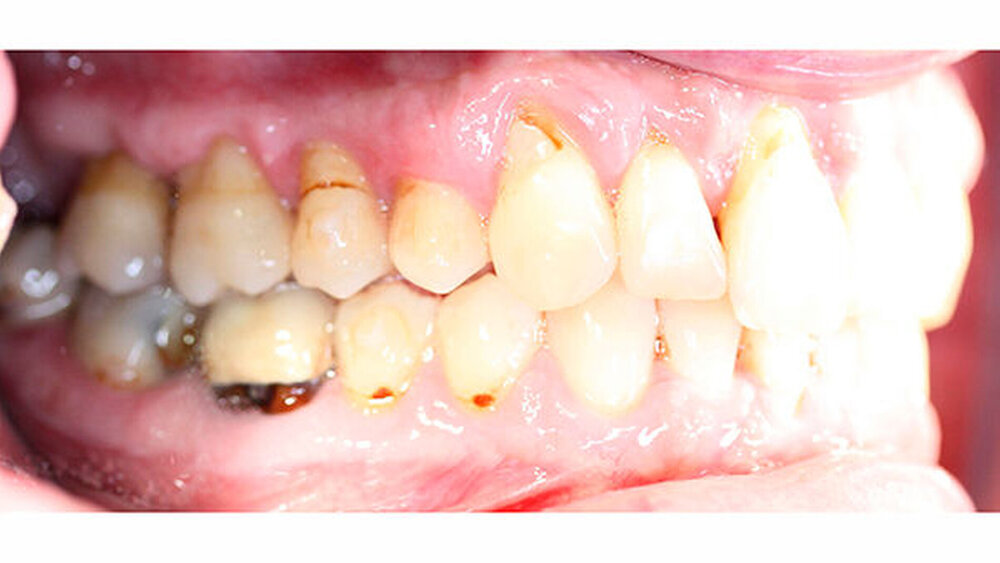

Intraoral zeigte sich ein bereits konservierend versorgtes permanentes Gebiss mit aktivem und inaktivem kariösen Geschehen. Große Anteile der Zahnhälse lagen nach Zahnfleischrückgang in Kombination mit Knocheneinbrüchen frei. Zahn 27 wurde bereits extrahiert.

Eine Beurteilung der parodontalen Situation an Zahn 11 offenbarte mesial und distal Sondierungstiefen von jeweils 6 mm.

Kieferorthopädisch imponierte beidseits eine neutrale Verzahnung bei einem tiefen Biss von 5 mm - bedingt durch die Verlängerung beider Frontzahngruppen. Besonders Zahn 11 zeigte eine erhebliche Verlängerung und Protrusion mit einer sagittalen Frontzahnstufe von 5 mm. Sowohl die Frontzähne im Ober- als auch im Unterkiefer wiesen eine lückige Beziehung zueinander auf (Abbildung 1).